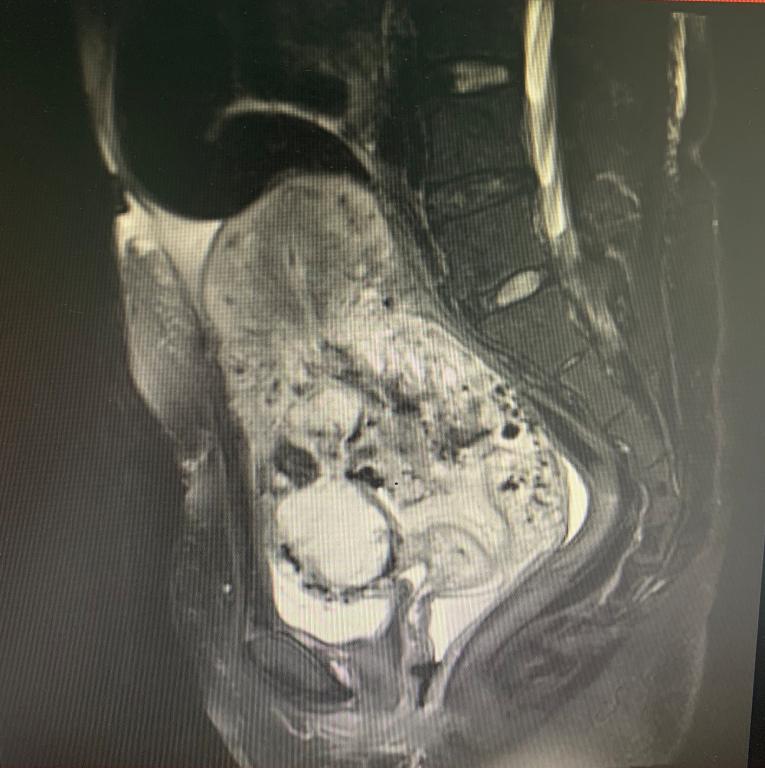

经过各方面的检查,袁女士被诊断为“胎盘植入”。阳华介绍,胎盘植入指胎盘绒毛穿入子宫壁肌层,是妇产科严重的并发症之一,可导致产妇大出血、休克、子宫穿孔、继发感染,甚至死亡。其中,穿透性胎盘植入更为凶险。

袁女士的诊断结果便是穿透性胎盘植入,胎儿娩出以后胎盘无法排出,未排出的胎盘不仅穿透子宫疤痕全层,还累及膀胱壁,因胎盘穿透性生长后周围血供很丰富,导致阴道反复出血,严重会危及生命。